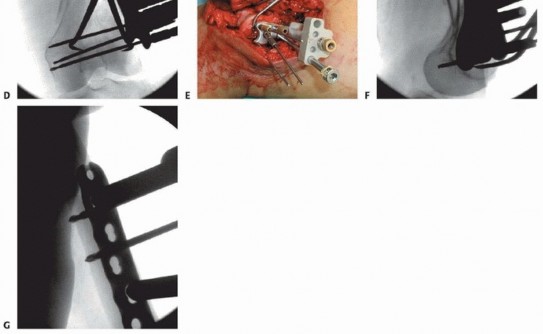

### FIG 5 • A-C. Patient with a spiral distal-third femur fracture that appears to be extra-articular. A. In the AP radiograph, the knee is not fully visualized. B. A dedicated knee AP radiograph shows the spiral distal-third femur fracture. Note the intra-articular injury and the gap at the fracture (arrows). C. Lateral view of the knee. Again note the coronal fracture of the medial femoral condyle (type B3). D-F. Plain radiographs of a patient with a grade II open distal femur fracture. G,H. Patient with a dosed femur fracture that was initially thought to be extra-articular. 470

---

### FIG 6 • A. Axial CT image of patient in FIG 5A-C confirming the type B3 fracture of the medial femoral condyle. B. Axial CT image of the patient in FIG 5D-F. C-E. CT images of the patient in FIG 5G,H show the nondisplaced intercondylar split as well as the low lateral fracture line and extensive posterior metaphyseal comminution (type C2).